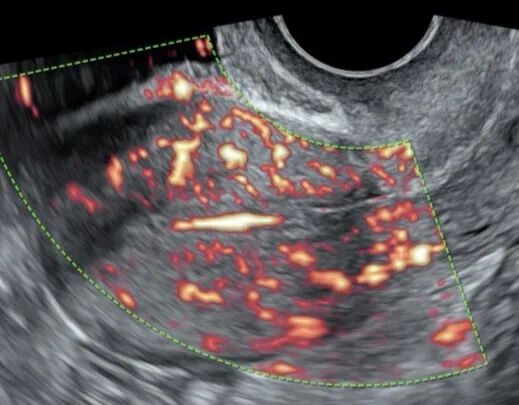

煊流成像技术:SlowflowHD:快速、直观显示微小血管

能否看清子宫内膜息肉的微小血管决定了诊断的准确性